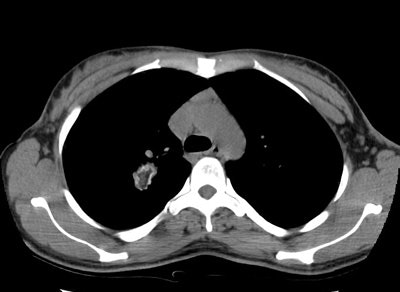

Pulmonary Hamartoma

The patient shown in the case below was referred for evaluation of a right upper lobe mass. The CT scan demonstrates a large mass in the right upper lobe that contained macroscopic fat consistent with a hamartoma. Lung windows demonstrated the lesion to be endobronchial and this was confirmed at surgical resection. (Click images to enlarge)